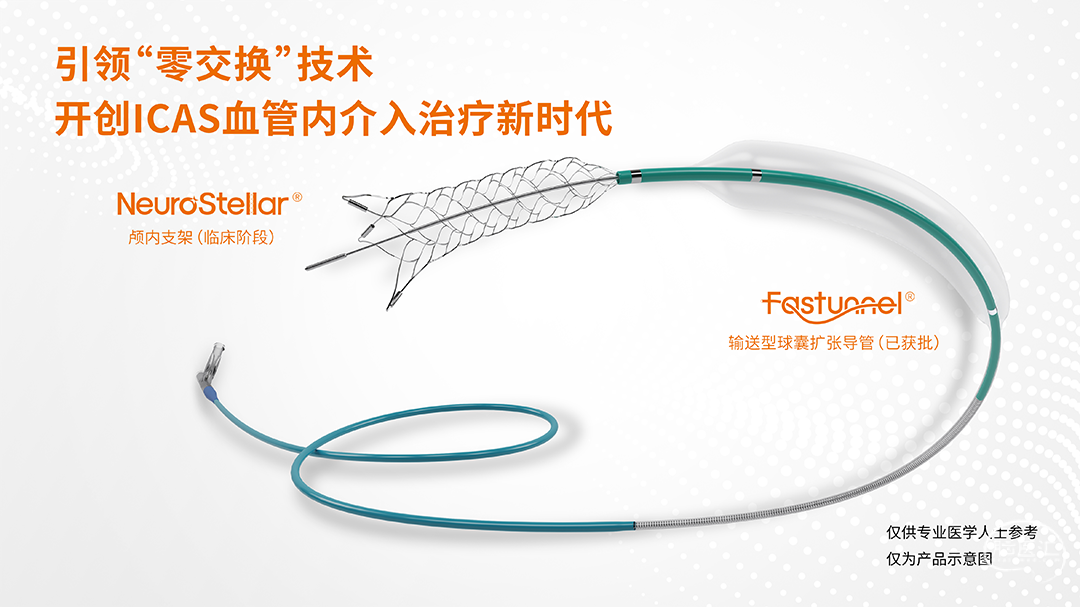

术中涉及介入器械选择

基底动脉远端双侧大脑后动脉纤细,血管迂曲,为减少器械交换造成医源性损伤。且球囊扩张后直接释放支架,选用21系列 Fastunnel®输送型球囊扩张导管 2.5*15mm压力泵缓慢扩张至命名压6atm。

经21系列 Fastunnel®输送型球囊扩张导管 2.5*15mm定位自膨式闭环支架 4.5*22mm(No Tip)。

经21系列 Fastunnel®输送型球囊扩张导管 2.5*15mm释放自膨式闭环支架后狭窄改善,双侧大脑后动脉、双侧小脑上动脉血管显影增强。

基底动脉非急性闭塞再通血管内治疗,微导丝、微导管顺利通过病变,微导管造影确认位于血管真腔。经快交球囊扩张基底动脉闭塞显示血流通过,此病例双侧大脑后动脉纤细、血管迂曲,过多器械交换增加基底动脉、双侧大脑后动脉医源性损伤风险,术中采用“球囊+微导管”一体化设计的Fastunnel®输送型球囊扩张导管,使用“零交换”技术可以一次性完成球囊扩张、支架释放等过程,减少了器械交换,简化操作步骤,减少透视时间,减少造影剂剂量,缩短手术时间,减少血管损伤,降低手术风险,提高手术安全性。